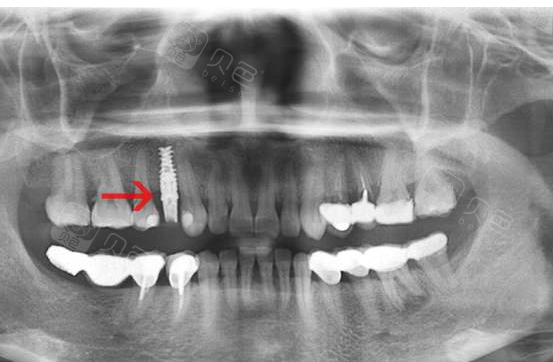

种植牙今天拍了个片子为什么种歪了

深圳种植牙怎样从牙片判断自己的种植体品牌呢